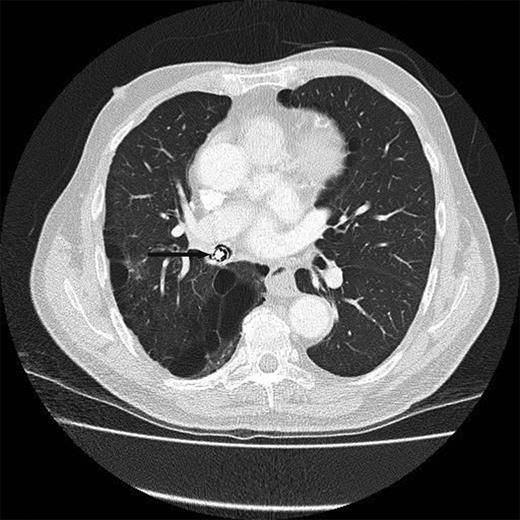

Chest X-ray (Fig. 1) and computed tomography (CT) scan (Fig. 2) revealed a foreign body in the right bronchus intermedius with collapse and consolidation of the distal bronchial tree. The gentleman was transferred to the cardiothoracic unit. An adult Negus rigid bronchoscope introduced under general anaesthesia revealed a metallic foreign body with smooth rounded contours wedged in the bronchus intermedius. This was removed using a Wolfe lighted grabber. The foreign body was a capsule endoscope (Given Imaging Limited, Israel) (Fig. 3).

CT scan showing the metallic object in and completely obstructing the bronchus intermedius.